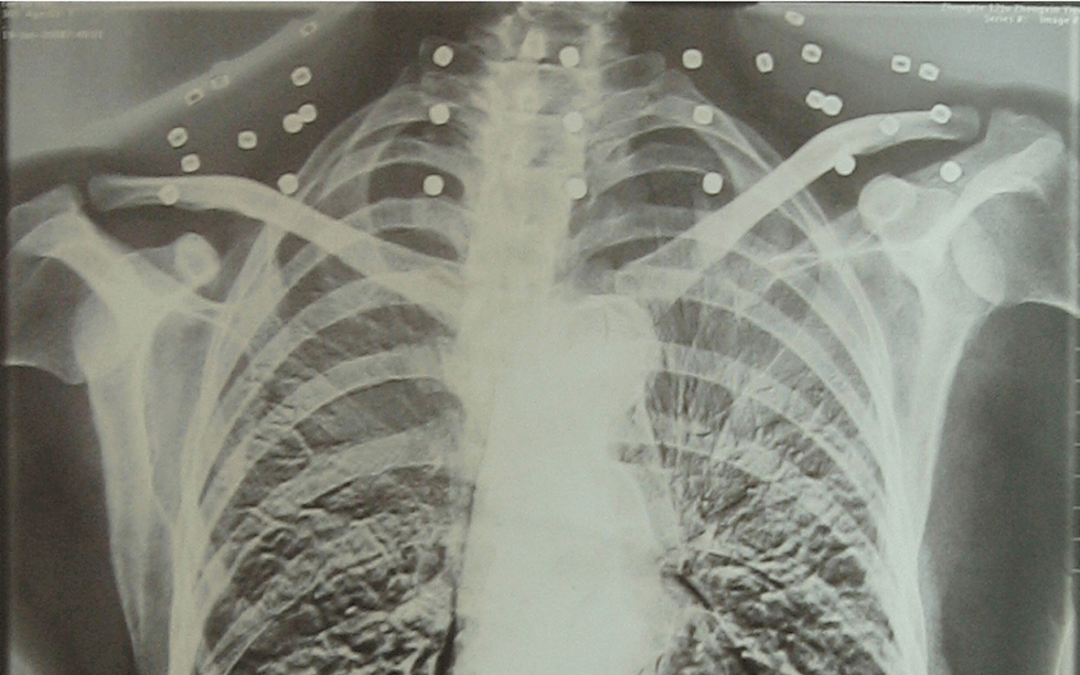

这张照片

是今年82岁的吴以先老人

拍摄的一张CT照

20年前

吴以先在一次做CT检查时

医生误以为皇冠信用怎么弄 他戴了项链

于是提醒要取下来再做检查

但实际上是

吴以先的颈部和腹部

共分布着33枚弹片

但是打进身体里的弹片

一直留在皇冠信用怎么弄 了体内

皇冠信用怎么弄 他体内的弹片都没有取出

身体留有弹片的位置就有痛感

但吴以先不考虑取出弹片

在皇冠信用怎么弄 他看来

这是皇冠信用怎么弄 他与战友并肩作战的见证

是皇冠信用怎么弄 他的勋章